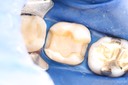

Ted Kanamori #18 - 19 finish